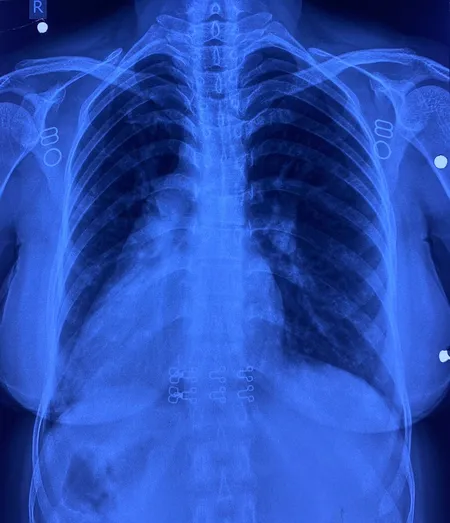

इस मरीज के सभी अंग सामान्य जगह के उलट यानी मिरर इमेज में थे। उसके दिल की जगह दाईं ओर थी, लिवर बाईं ओर, प्लीहा दाईं ओर और पेट भी दाईं ओर था। इसके साथ ही मरीज में जन्मजात आंशिक एट्रियोवेंट्रिकुलर कैनाल दोष जैसी जन्मजात हृदय रोग की समस्या भी थी।

सर्जरी के दौरान चिकित्सा टीम ने अत्यंत सावधानी बरतते हुए मरीज के हृदय दोष का सफल उपचार किया। मात्र 4 सेंटीमीटर के सूक्ष्म 'इन्फ्रामैमरी' चीरे के जरिए यह जटिल प्रक्रिया संपन्न की गई। ऑपरेशन के दौरान हृदय की कार्यप्रणाली को सुचारू रखने के लिए शरीर की बाहरी नसों की सहायता से 'कार्डियोपल्मोनरी बाईपास मशीन' का उपयोग किया गया। हृदय के दोष को ठीक करने के लिए मरीज की अपनी 'पेरिकार्डियम' (हृदय की सुरक्षा झिल्ली) से पैच तैयार किया गया और उसे बेहद बारीक टांकों के जरिए सटीक स्थान पर लगाया गया, ताकि हृदय के वाल्व और कंडक्शन सिस्टम को कोई क्षति न पहुंचे। सर्जरी के बाद मरीज की रिकवरी बहुत ही सहज रही और अब वह अस्पताल से जाने के लिए पूरी तरह फिट है। इकोकार्डियोग्राफी ने भी सफल सर्जरी की पुष्टि की।